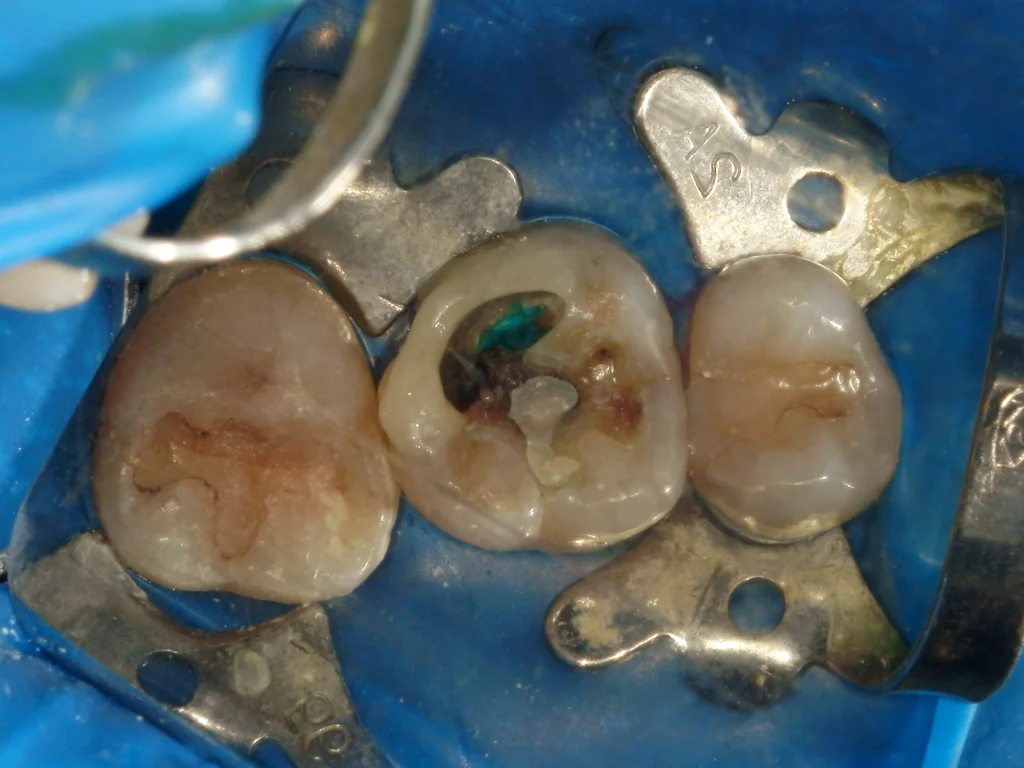

虫歯除去を再開し、すぐに歯髄が露出し出血してきました。

止血と消毒を行い、MTAセメントを貼付していきます。

1ヶ月経過後、セラミックの被せのために再来院していただきましたが、痛みは現在もないとのことです。